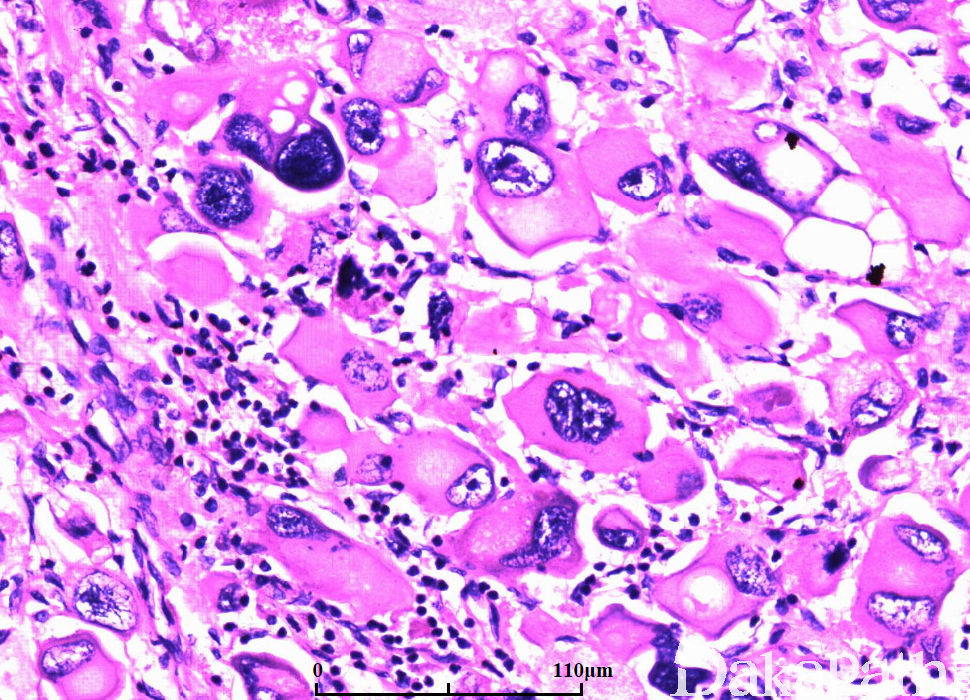

在非特殊型浸润性癌背景上出现 50%以上的显著多形性、形态怪异的巨细胞成分;

细胞异型明显,核分裂像多见(>20/10HPF),绝大多数属于 3 级;